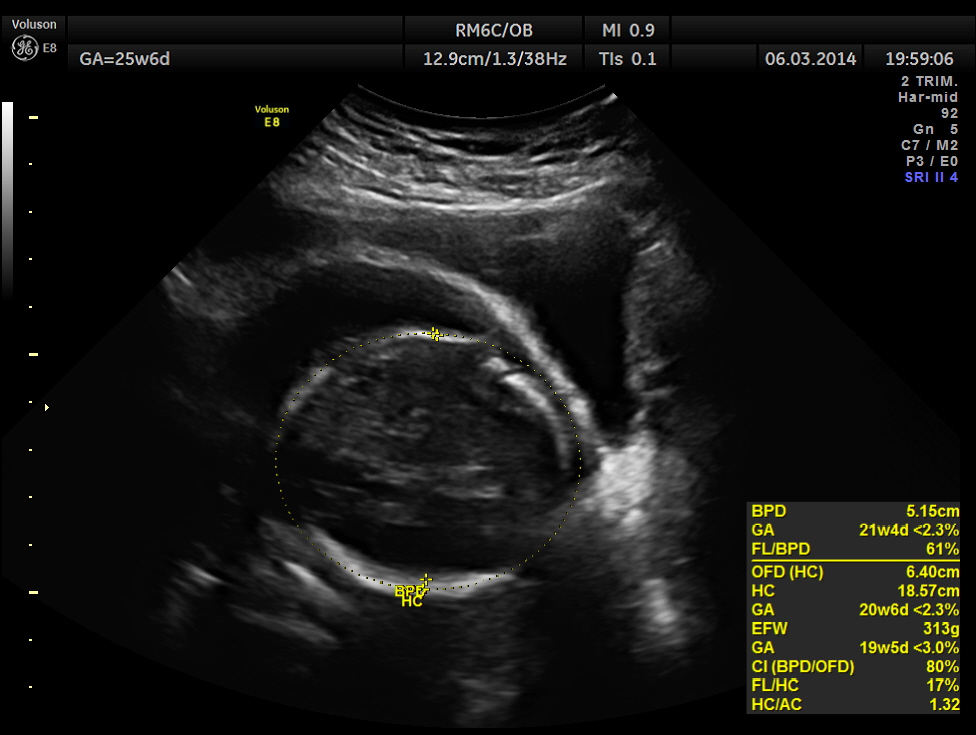

The GA was around 25 weeks , but the AUA was around 19 to 20 weeks. All parameters – BPD, HC, AC, FL are < 2.3 %tile and all other long bones are < 5.0 %tile.

Prominent placentomegaly seen .

At this point a diagnosis of Placentomegaly , Symmetrical Intra Uterine Growth Restriction , Probable renal dysplasia with oligohydramnios was suggested . The patient was referred by her consultant to a higher centre . The patient opted for termination of pregnancy as the 2nd opinion was also not favourable. But she had a spontaneous abortion few hours before the planned procedure. The fetus and the placenta underwent autopsy . The findings are summarised below :